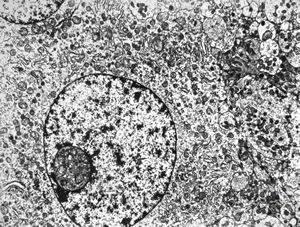

F,24y. | gangliocytoma

F,24y. | gangliocytoma

F,24y. | gangliocytoma

F,24y. | gangliocytoma